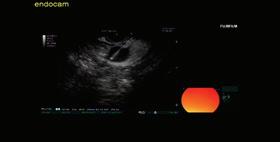

Доц. д-р Цветелина Тотомирова

48 КИСТИ НА ПАНКРЕАСАЗНАЧЕНИЕ, ДИАГНОСТИЧНИ ДИЛЕМИ И ИНДИКАЦИИ ЗА ХИРУРГИЯ Н. Шумка, П. Карагьозов

60 РАДИОФРЕКВЕНТНА АБЛАЦИЯ НА ПАНКРЕАСНИ ТУМОРИ ПОД ЕНДОСОНОГРАФСКИ КОНТРОЛ Й. Петкова, П. Карагьозов, И. Тишков УРОЛОГИЯ